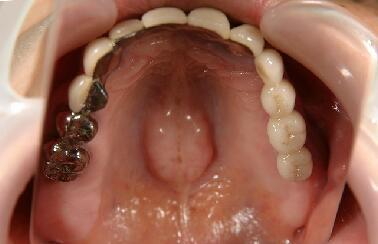

左上(写真では右の上となります)に最終かぶせ物(メタルボンドポーセレン)を装着